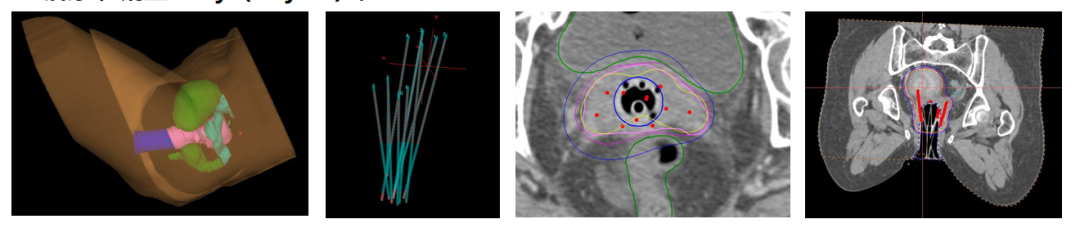

考虑到患者肿瘤大侵犯广泛,膀胱和盆腔侧壁高位侵犯,外照射结束后宫颈及双侧宫旁盆壁仍有明显肿瘤残留,因后装治疗进针路径通常为阴道,插值难度较大,较难布针布源满意达到合适的放疗剂量分布,同时患者对疼痛非常敏感,对后装治疗很抗拒。经治疗小组讨论后,与患者及家属沟通,拟予患者实施人工智能3D打印模板引导三维无痛插值后装治疗,鉴于是无痛和精准的治疗,患者和家属考虑愿意接受。

我们治疗上首先对患者进行模拟定位,制定出3D打印虚拟计划并设计针道,设计患者个体化3D后装模板,并制定周密个性化的精确放疗计划。麻醉科进行麻醉评估无禁忌症后,在B超实施超声引导给予患者行3D后装模板插植施源器植入。

后予患者行定位CT扫描,调整插值针位置深度,实时勾画三维后装靶区,放疗物理师制定出放疗计划,验证计划核查无误后,后装技师开始实施后装放疗。